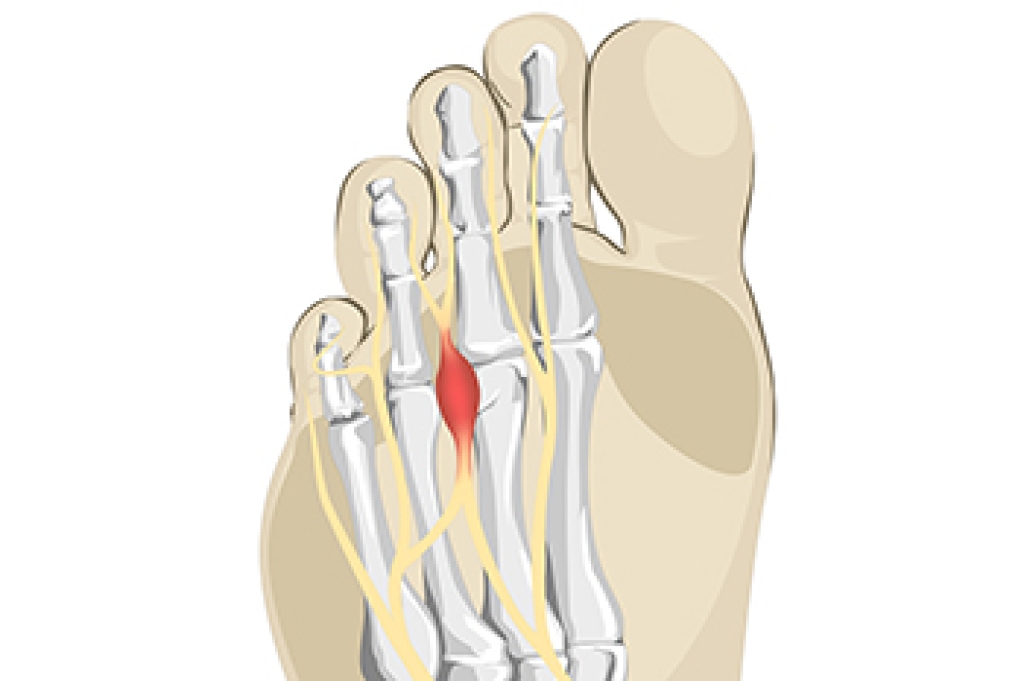

If your feet feel like they are burning up, it may be a sign that you have experienced nerve damage in the foot or leg, an injury, or a compression of the nerves. Burning feet, also known as Grierson-Gopalan Syndrome, is a condition that consists of damage to the small nerve fibers of the foot. Although the cause of this condition is not clear, it is often found in people who have diabetes, vitamin B deficiency, or rheumatoid arthritis. Among other possible causes of burning feet are peripheral artery disease, peripheral neuropathy, and Morton’s neuroma. Other factors that can result in burning foot syndrome include kidney or thyroid problems and abnormal biomechanics of the foot. Common symptoms of burning foot syndrome are a pain in the soles of the feet, a feeling of pins and needles, and numbness. If you regularly experience such symptoms, please contact a podiatrist for an exam and a diagnosis, followed by suggested treatment options.

- Bunions